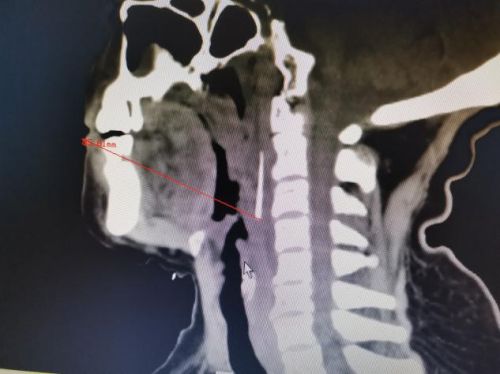

ct片上可以清晰地看到针状异物。

凌科技副主任医师接诊后查看CT影像发现,异物尖端位于老人口腔与食道入口上端,可谓“深藏不露”。手术团队讨论认为,如果经口腔入路切开咽后壁粘膜,由浅入深探查异物,虽然距离近,但异物小,位置隐匿,很可能寻找失败。第二套手术方案是经颈外入路探查,该方案优点是视野好,将重要解剖结构有效保护,找到异物的可能性较高,但存在异物刺破颈内动脉,引起大出血的可能。加上老人脖子粗短,术后咽腔水肿导致窒息的可能性大,届时就得进行气管切开,不仅手术创伤大,手术难度和风险也随之增加。